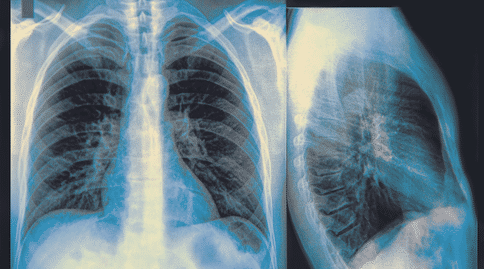

X線檢查 通過X線檢查可以了解肺癌的部位和大小,可能看到由于支氣管阻塞引起的局部肺氣腫、肺不張或病灶鄰近部位的浸潤性病變或肺部炎變。